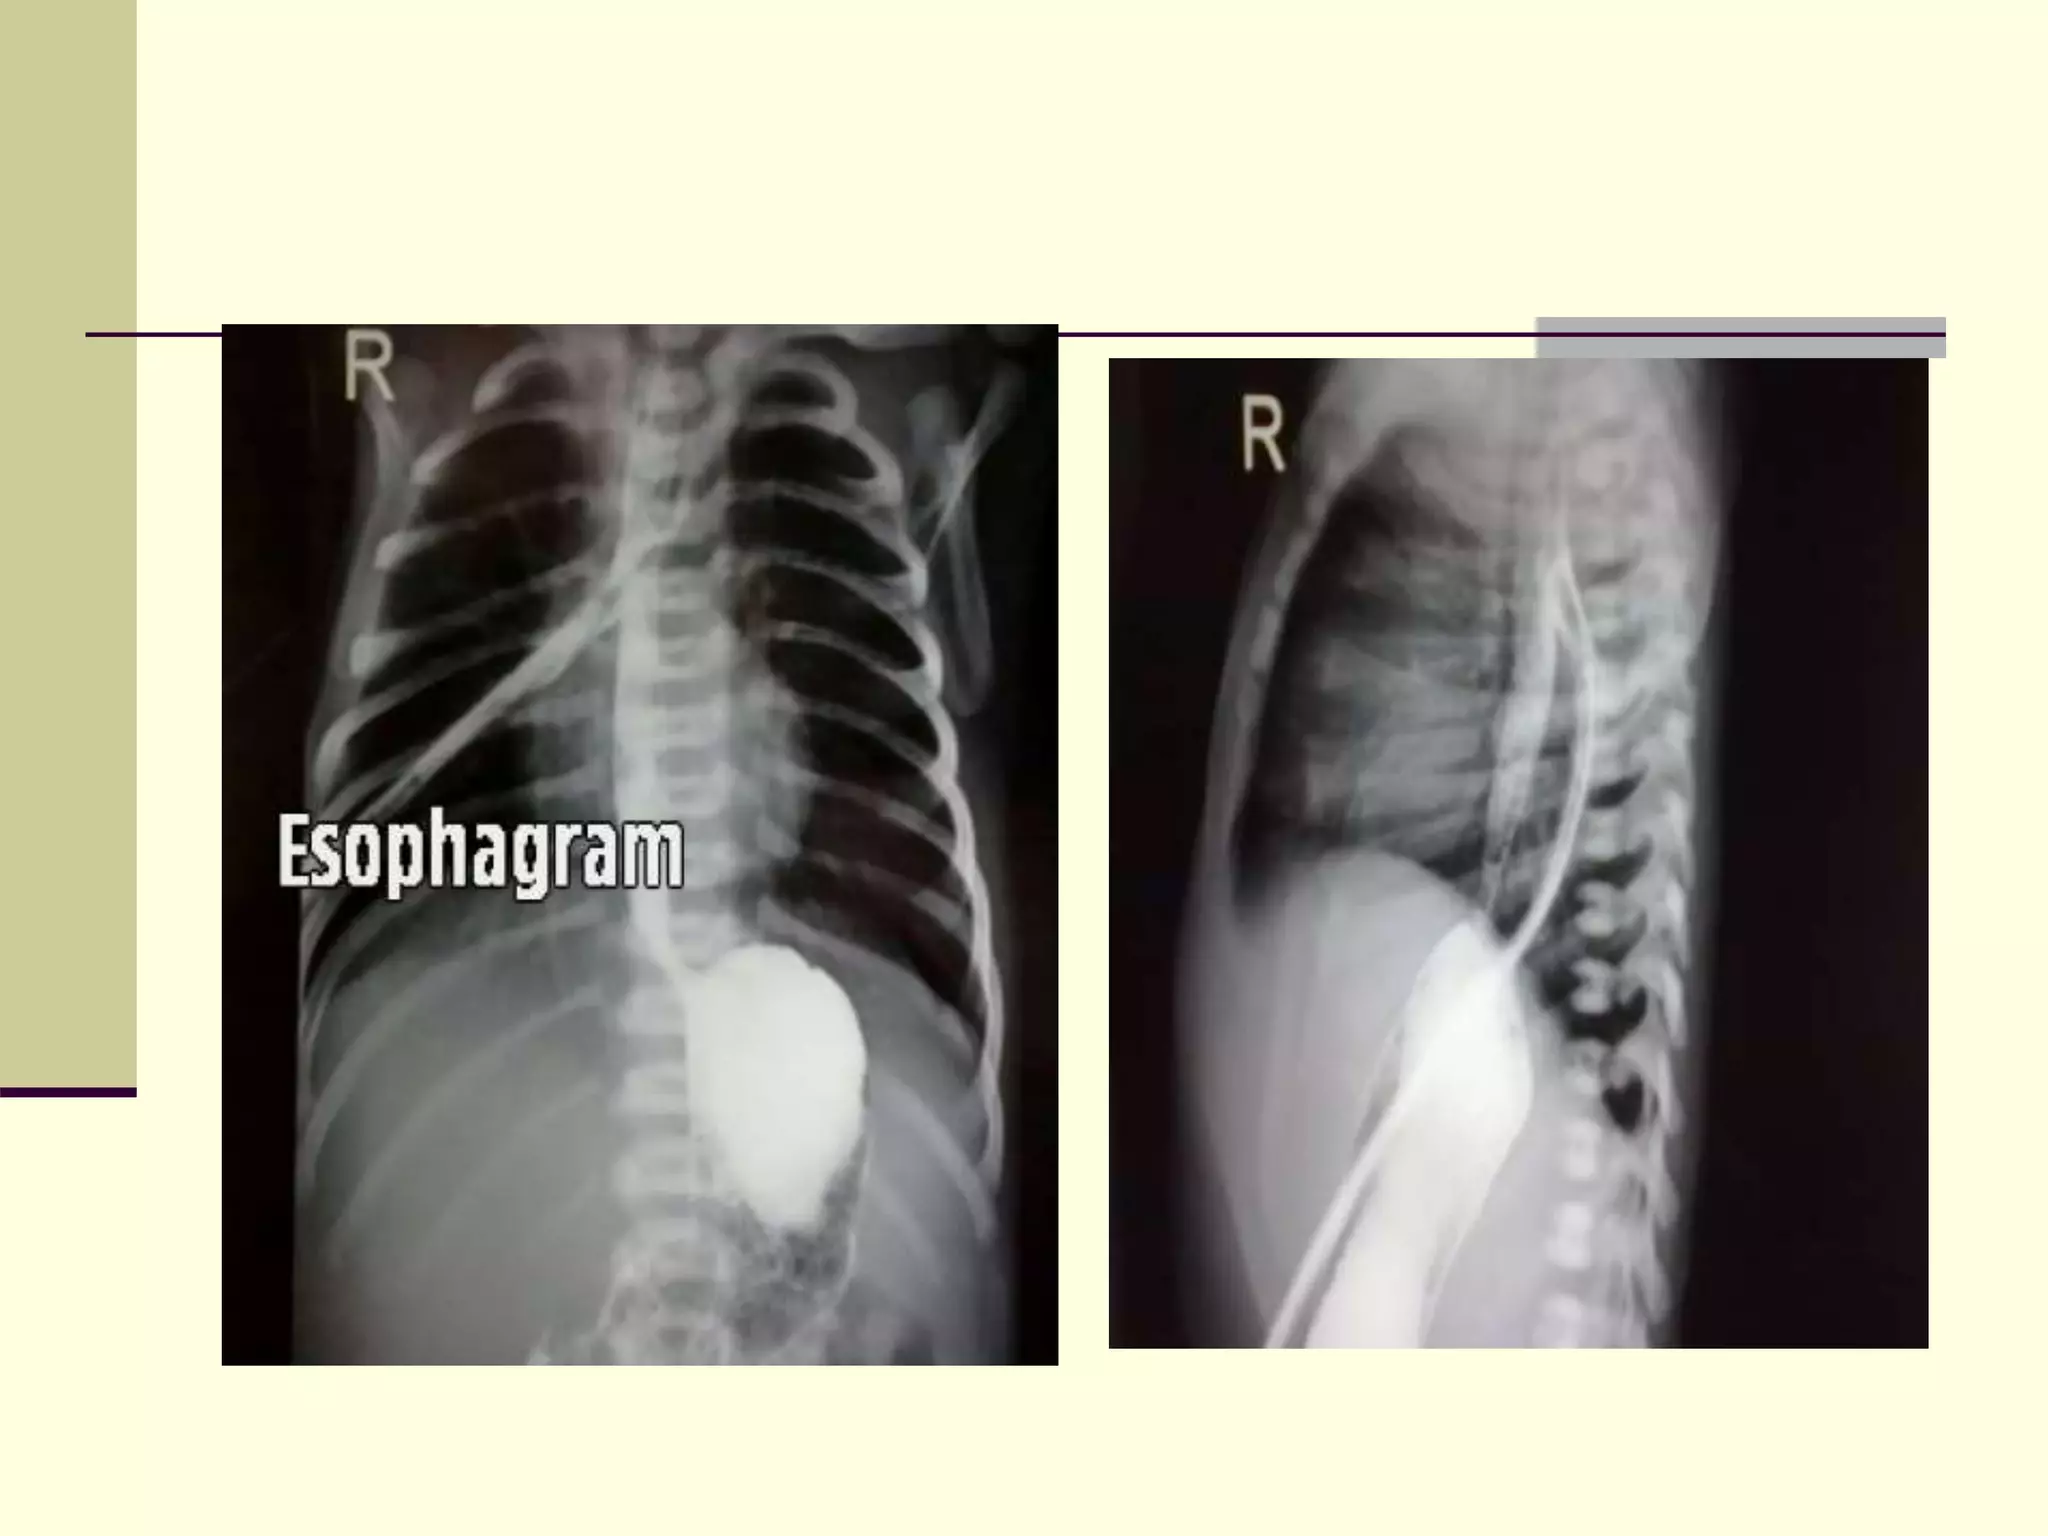

1) Plain AP – Lat radiograph

with

stiff red rubber catheter in situ

 Frontal view of the

chest and abdomen of

a neonate

demonstrates a tube

in the proximal pouch

in this patient with EA.

The presence of bowel

gas implies the

presence of a distal

TEF.

 : Contrast study with

demonstrating a

welldeveloped and

intact upper esophageal

pouch extending to

midthoracic level.

 H-type tracheoesophageal

fistula (TEF). Oblique

contrast esophagogram

demonstrates a fistula

(arrow) arising from the

anterior esophagus and

extending anterosuperiorly

to the trachea.